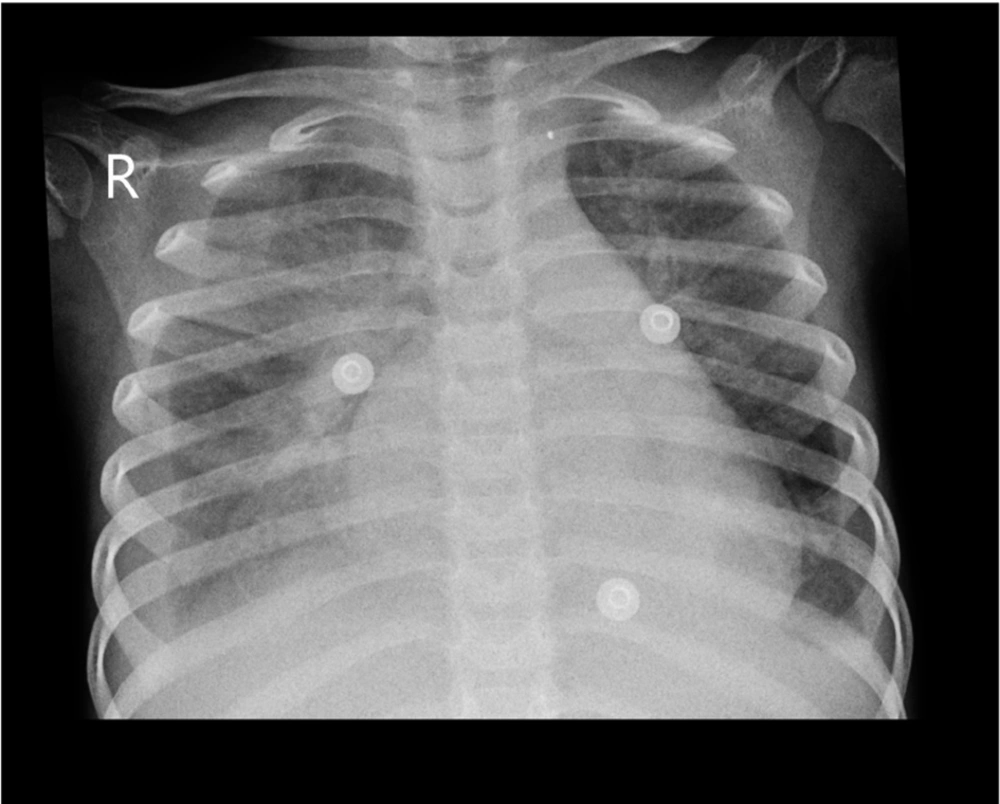

The patient, a 4-year-old girl with no known past medical history, presented with a recent episode of flu-like symptoms and abdominal pain persisting for 12 days without response to oral medications, culminating in severe respiratory distress. The parents denied consanguinity. Upon admission to the hospital, the child exhibited signs of respiratory distress, including tachypnea, decreased oxygen saturation levels, and the use of accessory muscles. Initial assessment revealed pleural effusion on chest X-ray, and after chest tube insertion, massive pleural effusion was observed. Heart sounds revealed a 3/6 murmur. Following chest tube insertion, the patient experienced a further drop in oxygen saturation, necessitating intubation. After intubation, negative pressure pulmonary edema occurred due to non-stepwise and large-volume pleural fluid drainage, presenting with pink foam discharge from the mouth and tracheal tube. Pleural fluid analysis showed cholesterol 9 mg/dL, TG 18 mg/dL, LDH 465 U/L, glucose 170 mg/dL, protein 1480 mg/dL, WBC 4, and RBC 1000 (Table 1). Aerobic and anaerobic pleural fluid cultures were negative.

Over the course of treatment, the patient’s respiratory distress gradually improved, with stabilization of vital signs and oxygenation. Serial monitoring of cardiac function and fluid status guided adjustments in inotropic support and diuretic therapy. Repeat imaging demonstrated resolution of pulmonary edema and pleural effusion, indicative of a favorable response to treatment (Figure 1). The patient was successfully weaned off ventilator support. Laboratory findings are shown in Table 1. Cardiac function returned to normal, and the child remained in a stable hemodynamic situation.